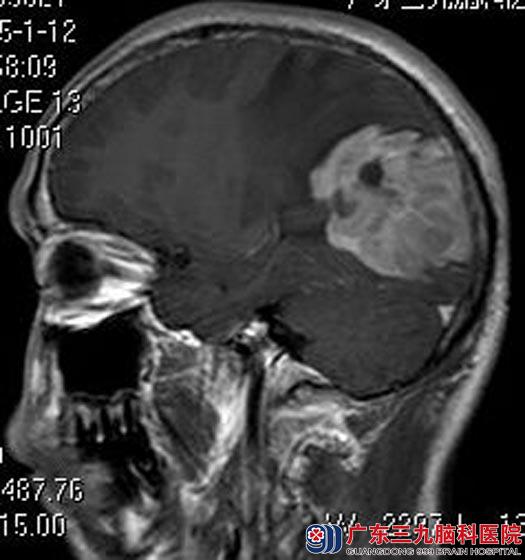

视物模糊逐渐加重,还伴有头痛、恶心等症状,当地医院头颅CT检查提示:右侧枕叶占位性病变;广东三九脑科医院进一步MR检查发现:右侧顶枕叶占位性病变,大小约7.38cm×4.25cm×5.72cm,考虑恶性肿瘤性病变。

完善相关检查后,由综合神经外科鲁明主任主刀,在全麻下行右侧枕叶肿瘤切除术,术中显微镜下见肿瘤位于枕叶皮层下,质韧,血供丰富,边界不清,与上矢状窦粘连,肿瘤长入上矢状窦内,镜下全切除肿瘤,手术过程顺利。术后李叔头痛症状较前好转,未再出现呕吐等不适症状。术后病理结果:弥漫性大B细胞淋巴瘤。